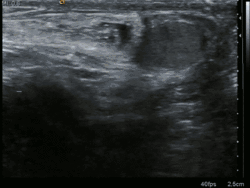

Диагностика

При обследовании больных при паховых грыжах проводится внешний осмотр в положении стоя и лежа обеих паховых областей для выявления в неясных случаях асимметрии, даже малозаметной, но дающей некоторые указания на возможное наличие грыжи. Намечается линия, определяющая положение паховой связки, для дифференциальной диагностики между паховой и бедренной грыжами. Определение этой линии несколько затрудняется при значительной полноте больного. Одновременно проводится осмотр обеих половин мошонки, определяется форма и величина яичек, также фиксируется и наличие расширенных вен семенного канатика. Натуживание больного, кашлевые толчки позволяют получить объективные данные и при внешнем осмотре в виде появления умеренного выпячивания соответствующей паховой области.

Ощупывание поверхностного пахового кольца при введении пальца и одновременном напряжении брюшной стенки (покашливание) даёт «симптом толчка».

Исследование поверхностного пахового кольца у женщин значительно сложнее, чем у мужчин, и удается лишь при дряблой коже и значительном расширении поверхностного пахового кольца.